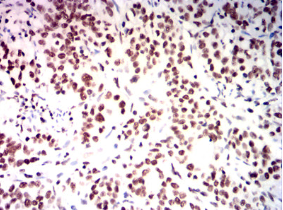

IHC    1/200 - 1/1000